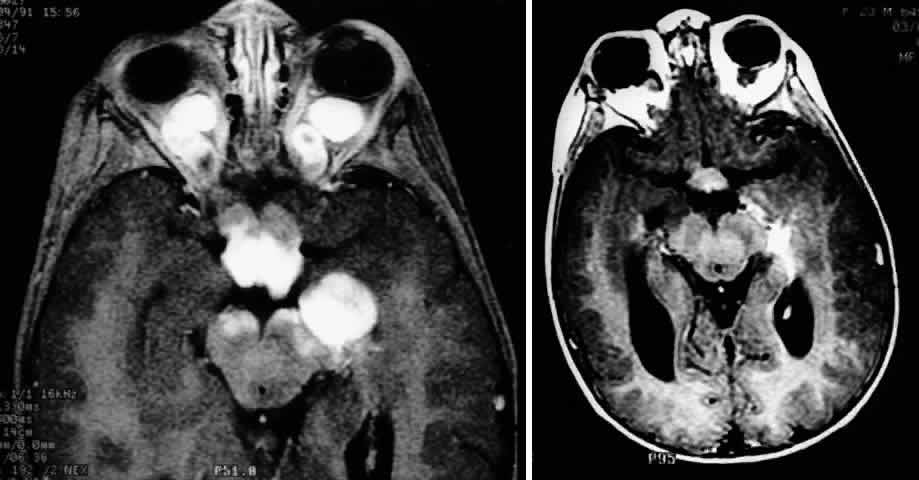

The use of chemotherapy for optic gliomas was prompted by the reported toxicity of radiation to the developing nervous system. Children irradiated before age 5 may have a tendency to incur behavioral and cognitive impairment.122 Results of chemotherapy for optic gliomas are difficult to interpret because of the sometimes indolent nature of these lesions, variably reported study follow-up periods, and small sample sizes. It does appear, however, that chemotherapy can effectively postpone radiation122 (Fig. 11 A and B). Unfortunately, there is little evidence that chemotherapy can provide long-term control of these tumors.20,122 In one series, approximately 60% of children treated for gliomas of the hypothalamus and optic pathways eventually had a relapse.122

Fig. 11. MRI scans demonstrating optic pathway glioma in a 14-month-old child with neurofibromatosis type 1, who presented with irritability and bilateral visual loss. The patient was treated with two courses of carboplatin and vincristine, resulting in marked visual recovery and a reduction in tumor size. Compare pretreatment MRI scan (A) with post-treatment MRI performed 5 months later (B). (Courtesy of Russell W. Walker, MD)